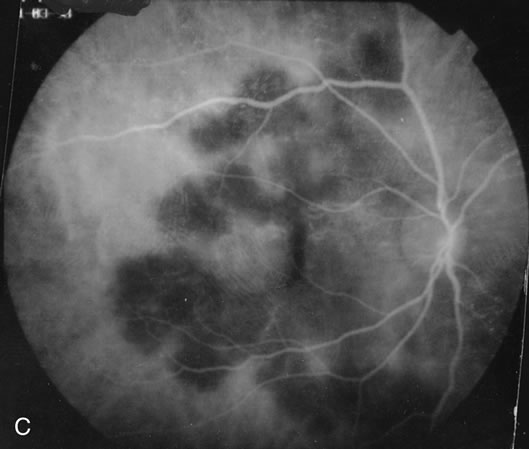

The classic findings in the acute cases are lesions of variable size that are hypofluorescent in the early phase of the fluorescein angiogram. In the late phases of the angiogram there is hyperfluorescence of the lesions. In the late phases, there also may be leakage from the disc as well, and there also may be staining of the retinal vessels because of the vasculitis. With resolution of the disease, there still may be a mottled pattern of fluorescence correlating with the areas of pigment clumping and pigment atrophy (Fig. 8).

Fig. 8. A. Early fundus angiogram showing hypofluorescence of the acute posterior multifocal placoid pigment epitheliopathy (APMPPE) lesions. B. Later stage of the angiogram showing staining of the APMPPE lesions.

Fig. 16. A. Color fundus photograph showing the jigsaw pattern of choroidal and retinal atrophy extending from the disc along the arcades. At the inferior edge of the superotemporal lesion there is a recurrence noted by the grayness of the retina. B. Fluorescein angiogram in the laminar venous phase showing a large window defect in the area of inactive choroiditis and blockage of the choroidal fluorescence in the area of active choroiditis. C. In the late phase of the fluorescein angiogram there is staining of the edges of the inactive choroiditis and marked hyperfluorescence in the area of active choroiditis.

Fig. 17. A. Classic inactive case of serpiginous choroiditis showing the jigsaw pattern of disease surrounding the fovea. B. Fluorescein angiogram showing staining of the edges of the inactive serpiginous choroiditis. There is blocked fluorescence in the areas of hyperplasia of the retinal pigment epithelium. C. Indocyanine green angiogram showing absence of fluorescence in the area of inactive choroiditis.